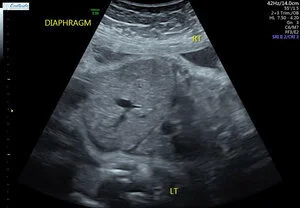

On January 31st 2018, I went in for a routine 32-week checkup. My daughter constantly kicked me in the ribs, but I mentioned to the doctor that she was a little less wiggly, so he ordered a non-stress test and an ultrasound. Braxton Hicks contractions and a strong heart beat. Perfect. Then the quickest ultrasound ever. After waiting for 45 minutes, the doctor pulled me back into his office and said that my daughter’s heart was strong and he doesn’t have any concerns for that. Then he broke me. He said my daughter has a hole in her diaphragm which is causing her internal organs to push on her lungs and is keeping them from growing. He immediately made an appointment for the high risk OBGYN across the street because they don’t deal with high risk pregnancies at this office. He apologized then left. To say I was heartbroken is an understatement. I immediately started googling diaphragmatic hernias and tried to find some reason as to why this happened. The diaphragm fully forms by week 12. At that time, I was 2 weeks away from getting married. My stress levels were through the roof. I worked at a coffee shop and drank 1-2 cups of coffee a day. Could that have been it? I drove myself mad trying to find a reason. Fast forward 2 months, and I have gone through most of the stages of grief. I was stuck on anger and sadness the longest. We met with genetic counselors, multiple surgeons/specialists, social workers, different OBs, and finally came up with a game plan.